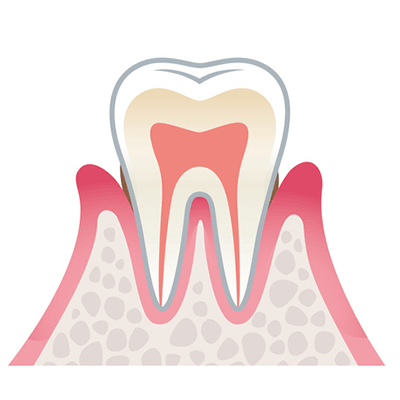

健康な状態

歯ぐきは薄いピンク色で引き締まっており、歯と歯ぐきのすき間(歯周ポケット)もなく、ブラッシングしても出血しません。

この状態を保つことが、歯周病予防の第一歩です。